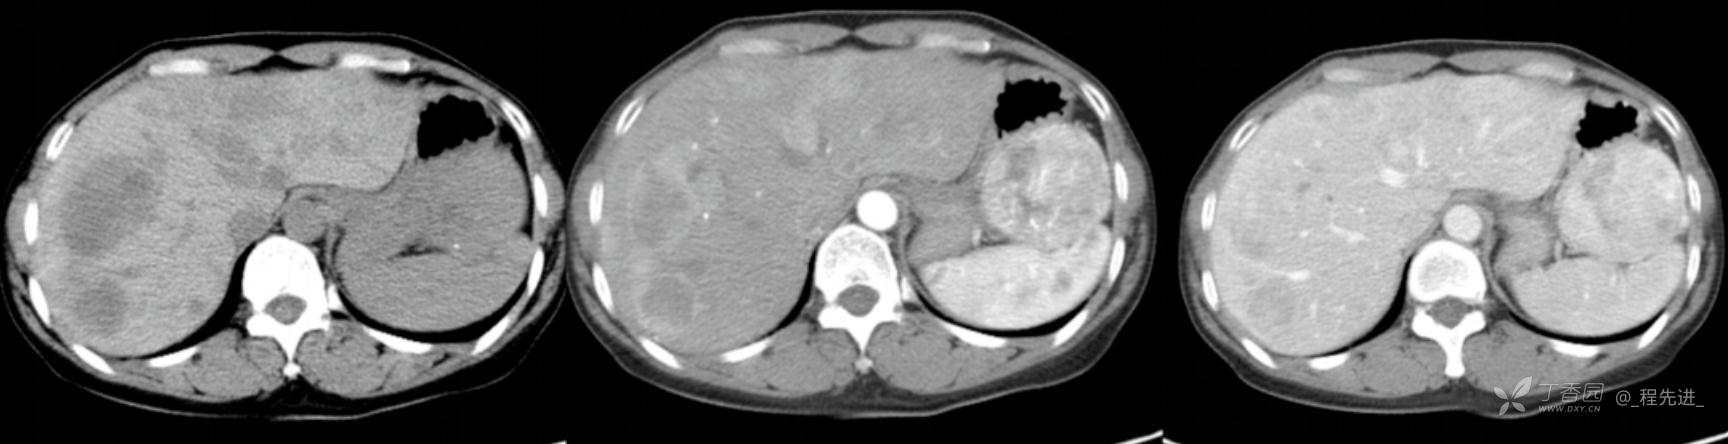

图像左边为平扫,中间的是动脉期,右边的是静脉期